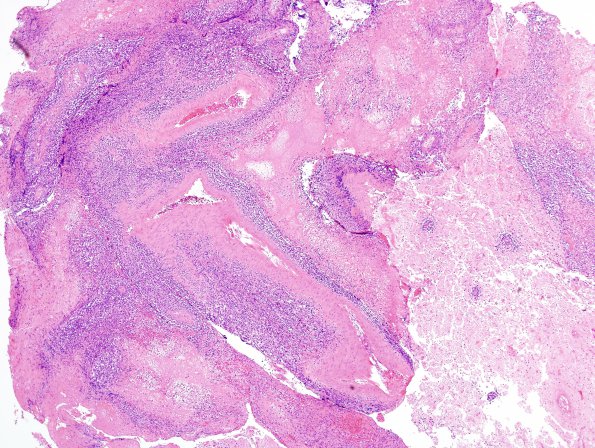

Washington University Experience | NEOPLASMS (HEMATOLYMPHOID) | Lymphoma, primary | 8A2 Lymphoma p 10days steroids (Case 8) H&E 3A

8A2-4 The neoplasm is composed of markedly atypical cells and a high nuclear to cytoplasmic ratio in a perivascular distribution. There is extensive tumor necrosis. (H&E)